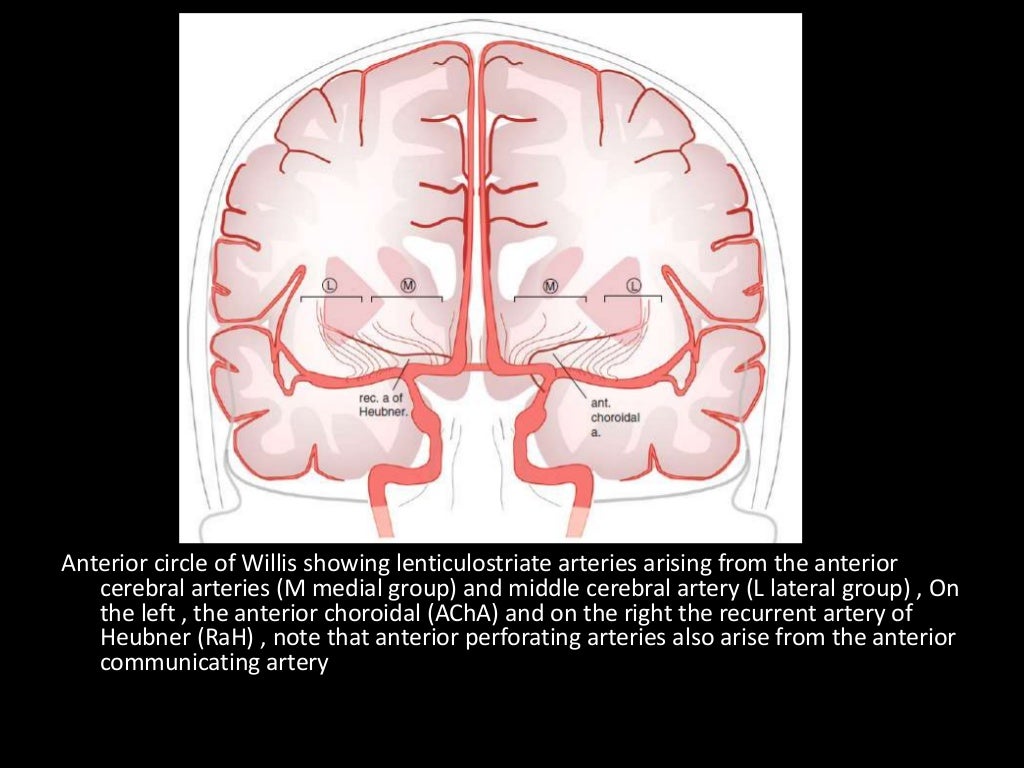

Perforating branches supply anterior limb of the internal capsule, inferior portions of caudate head and anterior globus pallidus.

Medial lenticulostriate A.

Recurrent artery of Hubner (= medial striate A.). Supplies head of caudate and anterior limb of IC. (Can be A1 branch)

NB Striatum = Caudate + IC + lentiform nucleus (which = putamen + GP).